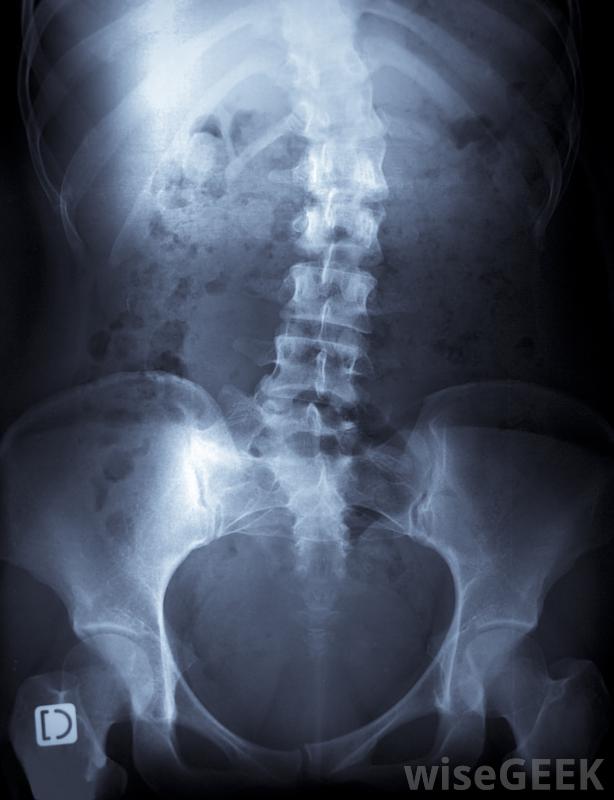

患者的身體癥狀,摸摸脊柱和周圍組織,并拍背部x光片。為了做出正確的診斷,醫生可能會進行額外的檢查,以確定潛在原因。有些脊柱側凸是先天性缺陷、神經肌肉疾病和關節炎所致不過,這種情況通常是特發性的,這意味著無法確定病因。

脊柱側凸是脊柱側彎的一種骨骼畸形。脊柱側凸的最佳治療方法取決于許多因素,包括彎曲的嚴重程度和位置,畸形的根本原因,以及患者的年齡。仍在成長中的兒童和青少年通常安裝有有助于使脊柱更直的支架。患有嚴重脊柱側凸的...

脊柱側凸是脊柱側彎的一種骨骼畸形。脊柱側凸的最佳治療方法取決于許多因素,包括彎曲的嚴重程度和位置,畸形的根本原因,以及患者的年齡。仍在成長中的兒童和青少年通常安裝有有助于使脊柱更直的支架。患有嚴重脊柱側凸的成人和年輕人通常需要進行手術以減輕疼痛并防止病情惡化。持續的物理治療和頻繁的檢查可以幫助他們確保脊柱側凸治療的成功。